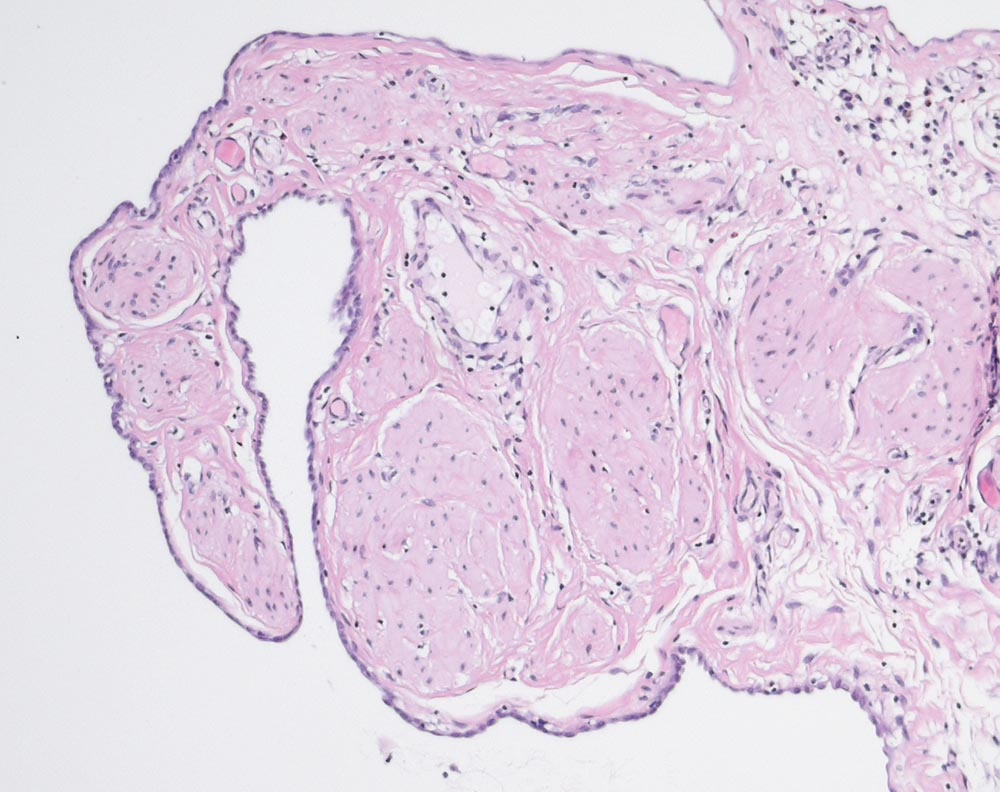

Nuck'sche Zyste

Mesothelausgekleidete Zyste des Processus vaginalis peritonei und Anteile des Ligamentum rotundum.

Nuck'sche Zyste rechts bei offenem Processus vaginalis. Schmerzen rechte Leiste

Histologie

100